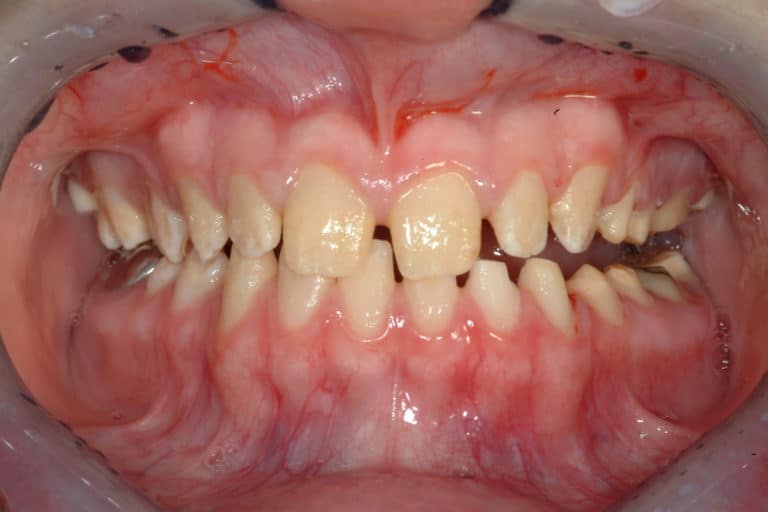

Before & After Gallery